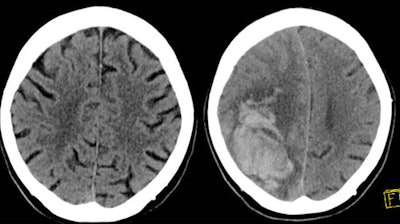

Adults who are on older blood-thinning medications have a significantly higher risk of a delayed intracranial hemorrhage (ICH) or death following brain trauma, according to research presented November 30 at the RSNA 2021 meeting in Chicago.

After conducting a retrospective study involving more than 1,000 patients with head trauma over three years, researchers led by Dr. Warren Chang of the Allegheny Health Network in Pennsylvania found that the group of patients who had been on older blood thinners such as clopidogrel (Plavix) and warfarin (Coumadin) had higher incidence of a delayed ICH occurring after the initial trauma and an initial negative CT exam.

Overall, 20 patients (1.91%) had a delayed hemorrhage and 3 patients (0.3%) died. All of the deaths were in the group of patients taking older blood thinners.